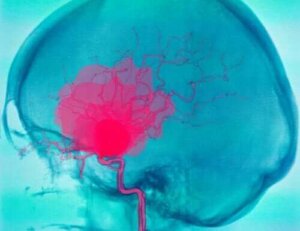

Subarachnoïdale bloedingen zijn bloedingen waarbij bloed tussen de arachnoïdes en de pia mater ophoopt. Het bloed komt meestal uit slagaders en kan veel verschillende oorzaken hebben. De meest voorkomende is een aneurysma, waarbij een bloedvat scheurt.